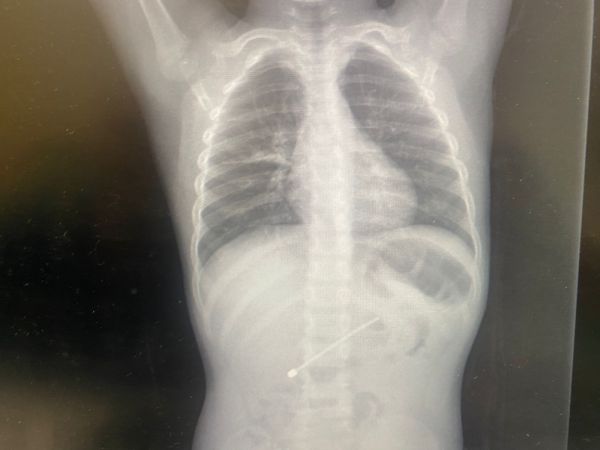

בתוך שלושה ימים: צוות רמב"ם שלף אנטנה מילד בן חמש, חתיכת פלסטיק מבסיס הלשון של בן שנתיים ופלסטלינה מדרכי האוויר של בן 8 חודשים